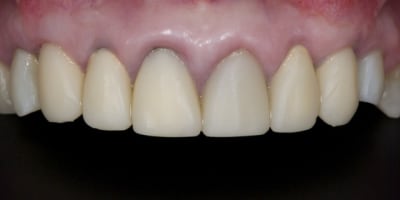

Exemple ici d'un cas ant avec

- une facette

- une ccm sur moignon metal implantaire

- une ccm sur inlay core

- une ccm a tenon.

Oui la CCM a encore de beaux jours.

Jolie prepa sur la 11.

16/03/2013 à 00h32

Très belles photos!

sur la 11 l'inlay core est en métal précieux ?

L'armature de la CCM 11 l'est elle aussi ?

Pour revenir au sujet "cas esthétique" , je trouve le bord libre de 11 un peu trop translucide.

Mais j'adore l'état du parodonte!